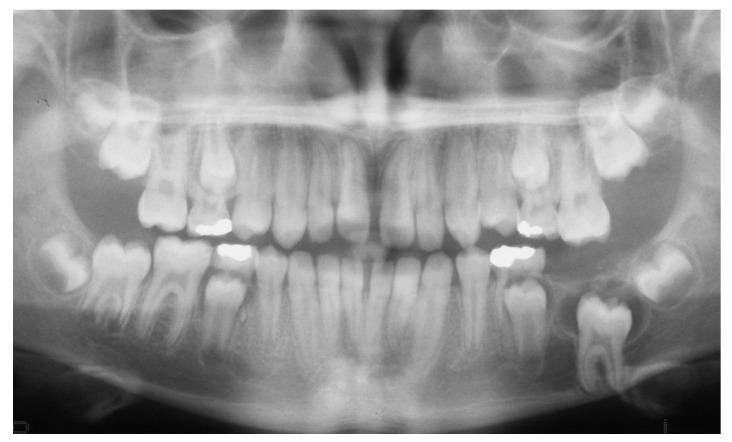

The purpose of this paper is to present a case of an impacted mandibular first molar associated with a dentigerous cyst and a missing mandibular second molar in an 11-year-old girl that was treated with combined surgical and orthodontic procedures. After clinical and radiographic evaluation, marsupialization of the cyst was decided, and a molar attachment was bonded on the buccal side of the impacted molar as a part of a full orthodontic treatment with fixed appliances. After 18 months of orthodontic traction, the molar was moved to a more advantageous position, and new bone apposition was observed on the site of the cystic lesion. Histological examination confirmed a dentigerous cyst. The molar was left to erupt spontaneously for 14 more months. A functional occlusion was finally achieved. An interdisciplinary approach proved to be an effective modality in treating a large dentigerous cyst associated with a deeply impacted first mandibular molar, presenting many advantages, such as new bone apposition and patient comfort.

本文旨在介绍一例11岁女孩的病例,该患者下颌第一磨牙阻生并伴有含牙囊肿,同时下颌第二磨牙缺失,采用手术和正畸联合治疗。经过临床和影像学评估后,决定对囊肿进行袋形术,并在阻生磨牙的颊侧粘结磨牙附件,作为固定矫治器全口正畸治疗的一部分。经过18个月的正畸牵引,磨牙移动到更有利的位置,并且在囊性病变部位观察到新骨形成。组织学检查证实为含牙囊肿。磨牙又自行萌出了14个月。最终实现了功能性咬合。跨学科方法被证明是治疗与下颌第一磨牙深度阻生相关的大型含牙囊肿的有效方式,具有许多优点,如新骨形成和患者舒适度高。